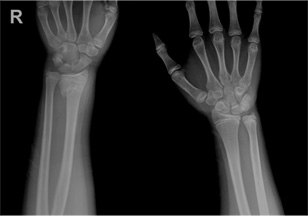

소아 손목 골절 수술 전

x-ray 사진